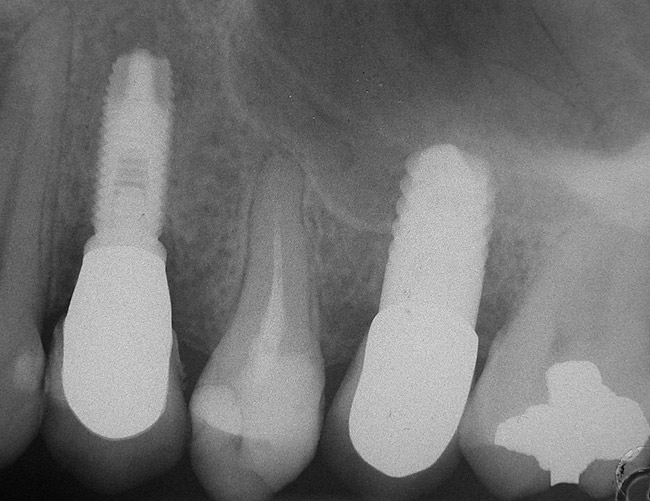

A 55-year-old male was referred for implant placement and prosthetic rehabilitation in the area of tooth No. 15. The tooth had been extracted 4 years prior. The radiograph revealed inadequate bone height for implant positioning (Figure 6). It was decided to insert an implant that was 11.5 mm in length and 3.75 mm in diameter, performing a slight osteotomic maxillary sinus lift. A heterologous bone graft also was planned to obtain a larger sinus lift.

A full-thickness mucoperiosteal flap was raised, and alternating osteotomes were used to prepare the implant site. After achieving a length of 7 mm (Figure 7A and Figure 7B), heterologous bone graft was implanted and the osteotome sequence was repeated. The implant showed primary stability.

Second-stage surgery was performed after 4 months (Figure 8); healing abutments were placed and the soft tissue was allowed to heal for 5 more weeks. Then, splinted porcelain-fused-metal (PFM) crowns supported by custom gold abutments were delivered (Figure 9 and Figure 10).

Figure 6  Preoperative radiograph of the area around tooth No. 15.

Figure 8  At 4 months after treatment, the radiograph revealed the presence of a bone layer surrounding the implant.